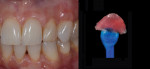

Anterior esthetics plays a significant role in restoring chipped or worn dentition. The patient shown in Figure 9 chipped the distal area of tooth No. 9 during a surfing accident. His goal was to restore the tooth to its natural shape and esthetics. Using additive techniques, the dental team eliminated the preparation stage and merely smoothed the tooth surface where the chip occurred to ensure there were no sharp angles. An impression was taken of the chip and an alveolar model was fabricated to restore the case using the refractory die technique (Figure 10). The refractory die was then burned out in a KDF burnout oven (KDF US, www.kdfus.com). This oven is preferred because it enables the technician to completely control the rise and stages of the degas cycle. Before the ceramic layering process begins, one must analyze the adjacent teeth to determine color selection (Figure 11). Although the chip was small, it was evident from studying similar situations on natural dentition that many different shades would be involved in restoring such a small space (Figure 12). Once the shading was analyzed and the ceramic colors and effects were determined, the ceramic layering was accomplished (Figure 13). The chip was finalized on the refractory die and then divested. Because of the fragile nature and size of the chip, the refractory material was cut with a disc in close proximity to the chip and then embedded in a silicone matrix (Figure 14). The silicone allows the restoration to divest without the chip blowing away. The restorative chip was then etched and finished with ceramic etching gel (Tri-Dynamics, Pearson Dental Supplies, www.pearson.com) and rinsed clean with hydrofluoric acid to ensure a strong bond (Figure 15). The chip was then affixed to a seating tool for easy handling, and wax was used to hold the chip steady for the try-in. Once in place on the tooth, the entire tooth and restoration are hydrated with water to determine if the chameleon effect had been achieved (Figure 16). The chip was then bonded to the remaining natural tooth structure and finished intraorally on the extended clear margins until a seamless effect was achieved (Figure 17). The final restoration exhibited the vitality of a natural

tooth (Figure 18).